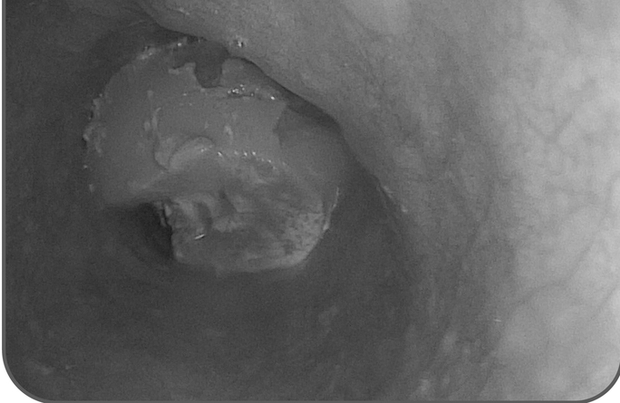

Bác sĩ Trương Minh Hiếu, Trưởng khoa Nội soi - Bệnh viện Đa khoa Xuyên Á Long An, cho biết vào ngày 13-6 vừa qua, bệnh viện đã cấp cứu thành công một bệnh nhân nam, 59 tuổi, bị hóc gân bò trong lúc ăn sáng. Người đàn ông này đã nuốt phải cục gân bò và cảm thấy đau vùng thượng vị cùng với các triệu chứng nôn ói và không ăn uống được. Sau khi được đưa đến Khoa Cấp Cứu - Bệnh viện Đa khoa Xuyên Á Long An vào khoảng 17 giờ cùng ngày, các bác sĩ đã nội soi và phát hiện khối thức ăn dai kích thước khoảng 6 cm bị kẹt ở 1/3 giữa thực quản. Chính vì vậy, các bác sĩ đã tiến hành can thiệp bằng cách dùng đầu ống soi đẩy khối thức ăn xuống dạ dày và kiểm tra không ghi nhận trầy xước. Qua đó, bệnh nhân đã ổn định sức khoẻ.